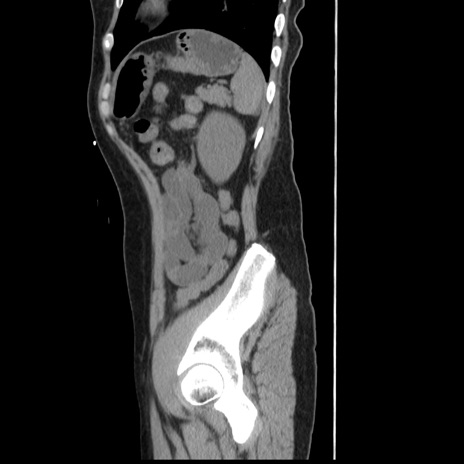

症例10(矢状断像)

【症例】 50歳代女性

【主訴】 腹痛

【現病歴】前日生レバーを食べた。今朝に排便あり。 昼前に突然発症の腹痛を生じ、当院救急外来を受診した。

【既往歴】 子宮筋腫にてで子宮全摘後

【身体所見】 意識清明、腹部:平坦、軟、下腹部やや左を中心に圧痛・反跳痛あり、筋性防御あり

【データ】WBC 7800、CRP 0.07